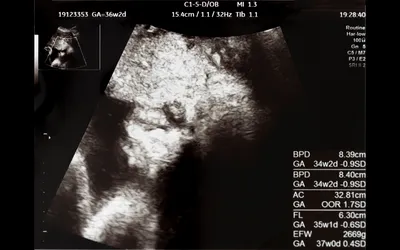

エコー写真には胎児についてのさまざまな情報が書かれていますが、多くがアルファベットを用いた略語で表記されています。

エコー写真の見方

日付時間:エコー写真が撮られた日時

GS:赤ちゃんが入っている胎嚢の大きさ

CRL:頭殿長。頭からおしりまでの長さ

GA:赤ちゃんの大きさから割り出した妊娠週数

EDD:検査結果から導き出された出産予定日の目安

+マークxマーク:赤ちゃんの大きさを測る際の目印(起点と終点)

BPD:児頭大横径。頭の大きさ

A×T:赤ちゃんの胃があるあたりの断面積

AC:赤ちゃんのおなか周りの長さ

FL:太ももの骨の長さ

これらの記号・アルファベットは一例です。

また、機械によって表記が異なることがあります。検査結果でわからないことがあれば、写真をもらったその場で医師に確認しましょう。